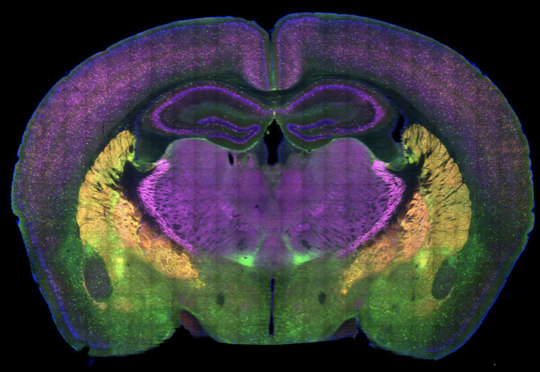

预测和更新不需要——通常也没有——意识的参与,大脑在多个潜意识层次建立模型。将近20年前,研究者揭示了视觉皮层使用的多层次、预测性的工作方式(Rao & Ballard, 1999, Nat. Neurosci. )。初级视觉皮层产生了对图像的小尺度特征的预测,比如边缘信息,然后试图通过完善预测来匹配视网膜的信号,但如果这局域化的微调不够,那它就把任务再甩给次级视觉皮层,后者再改进对更大尺度的几何特征的预期。随着层级向上,更广泛的变化被唤起,直到最高的层级:意识为止。(“预测性编码”一词是神经科学家从通讯工程中继承的,该术语在1950年代被建立,用来描述为减少所需要荷载的信息量,通讯网络只传递偏差而不是原始数据的想法。)